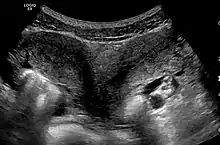

Ultrasound showing didelphys

Uterus didelphys (sometimes also uterus didelphis) represents a uterine malformation where the uterus is present as a paired organ when the embryogenetic fusion of the Müllerian ducts fails to occur. As a result, there is a double uterus with two separate cervices, and possibly a double vagina as well. Each uterus has a single horn linked to the ipsilateral fallopian tube that faces its ovary.